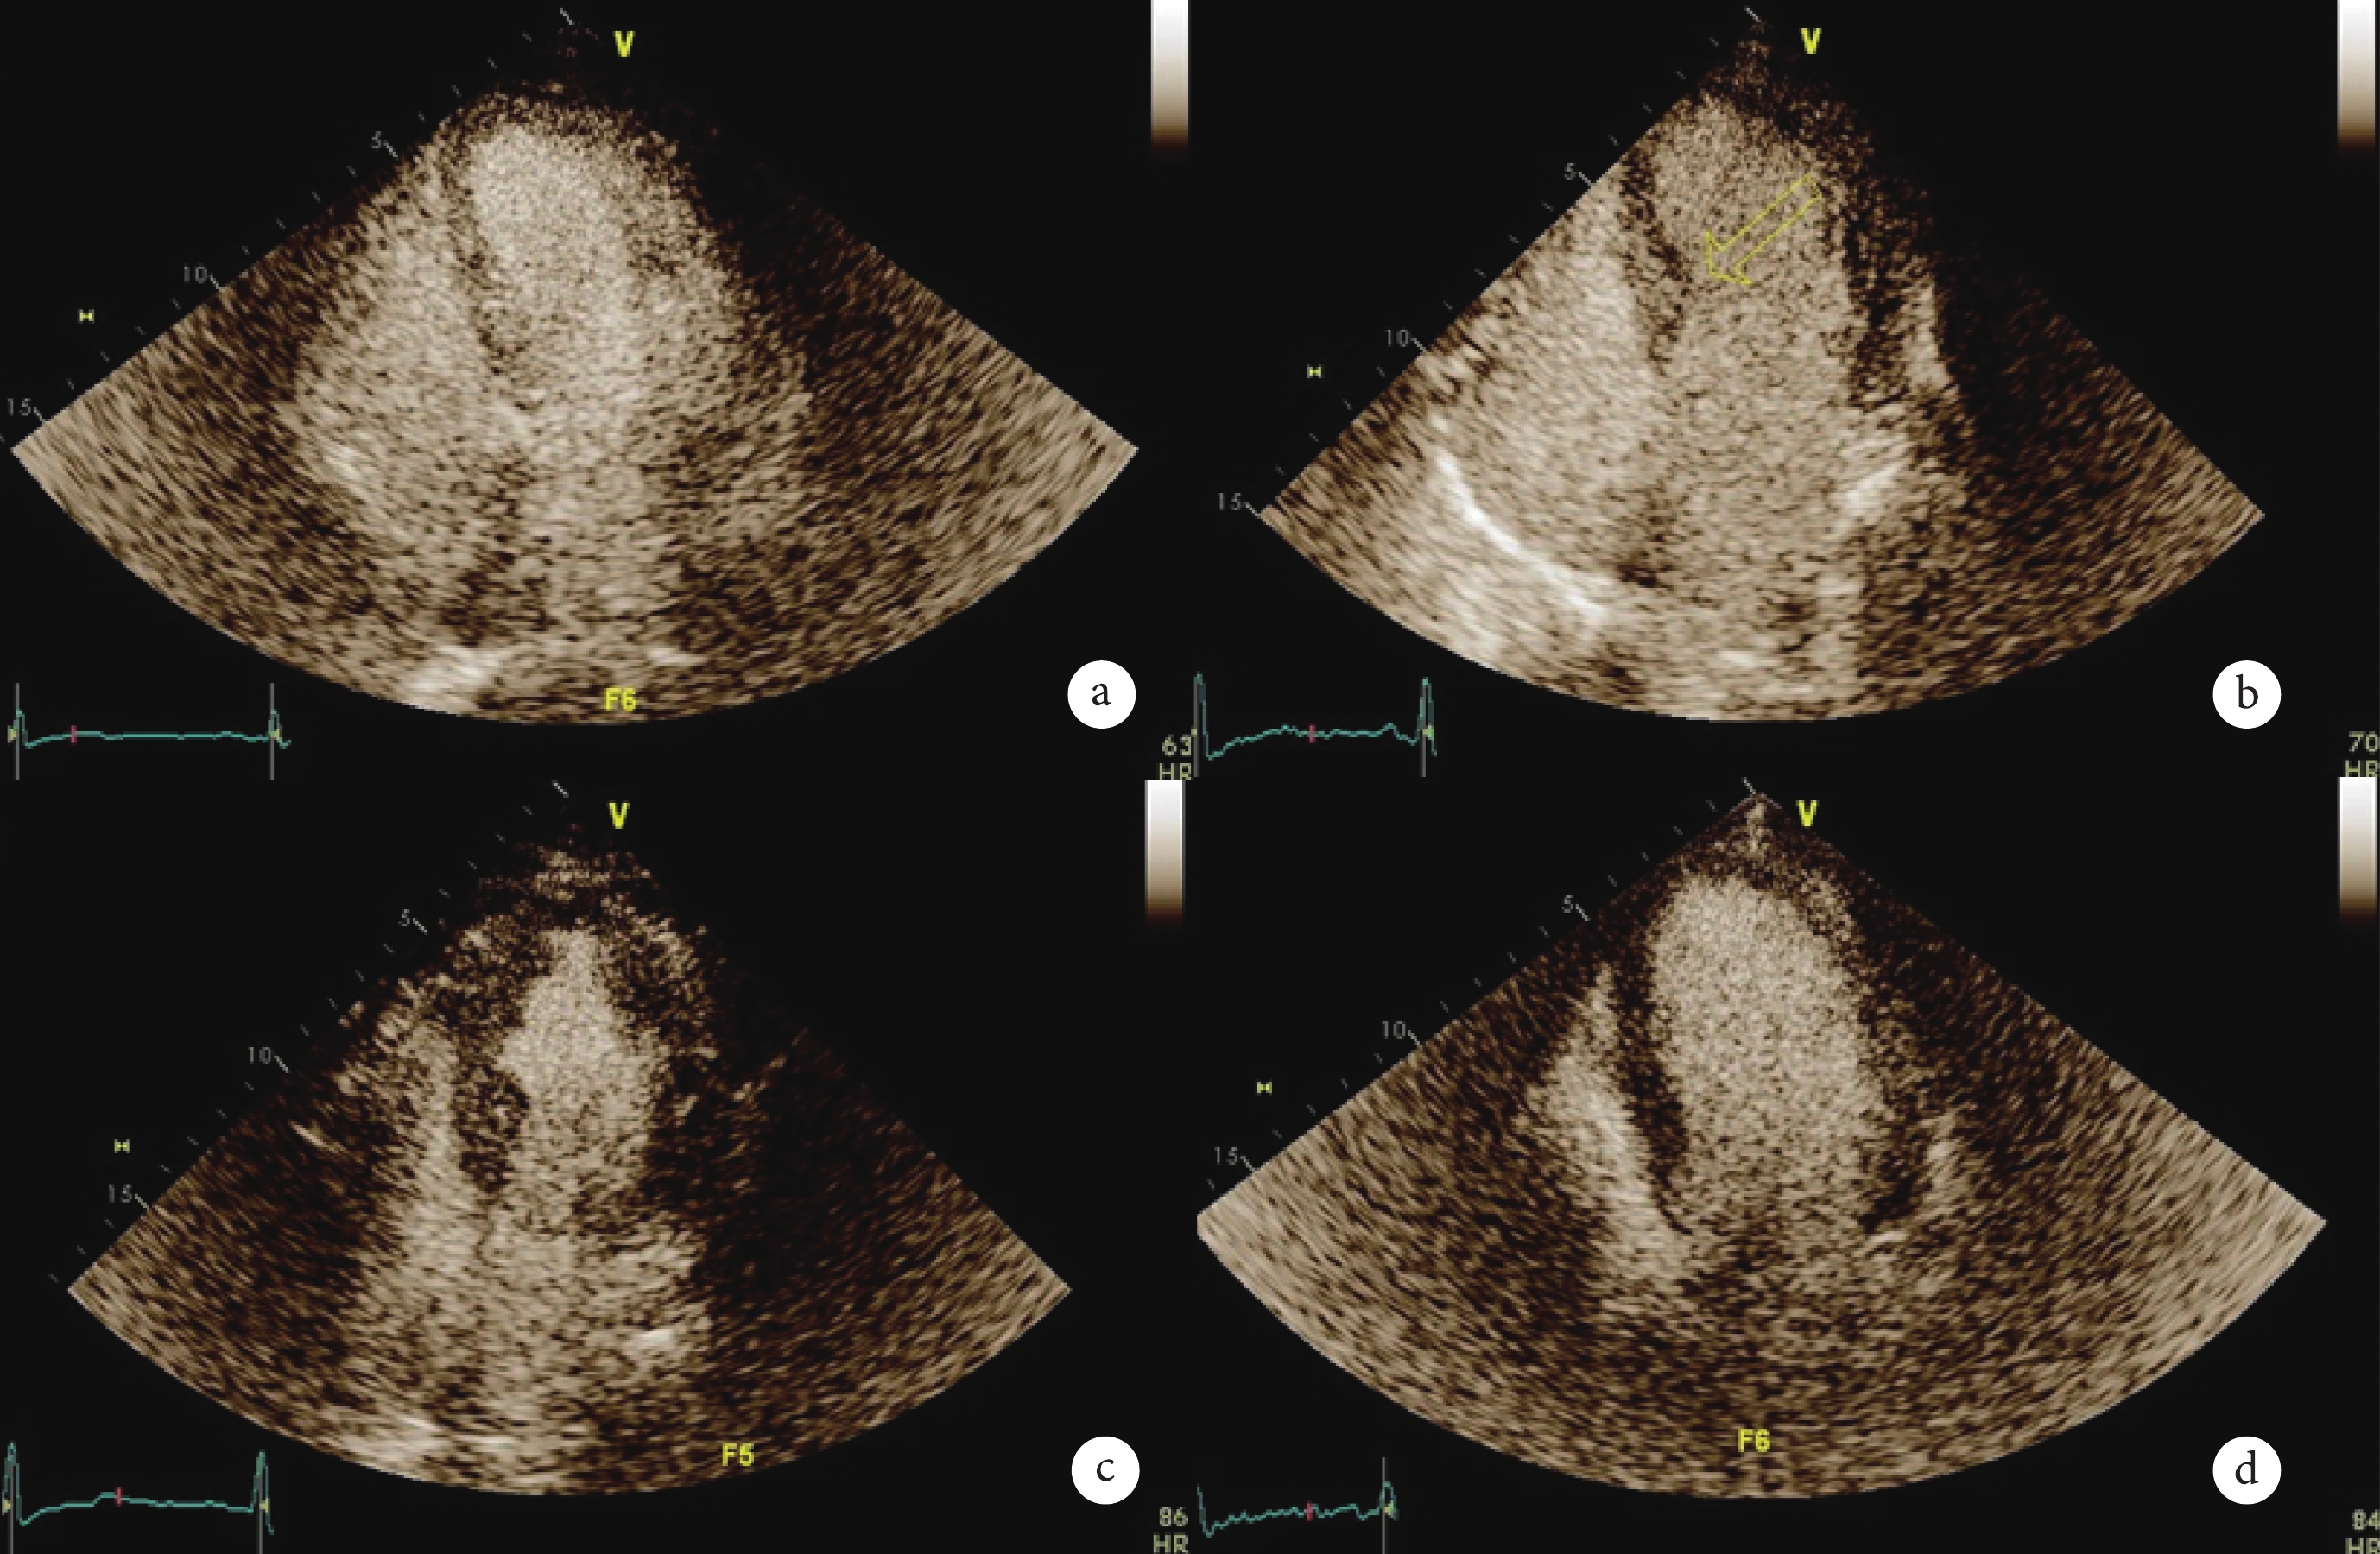

圖1

心肌灌注超聲檢查心肌灌注經典圖像

a:心肌灌注良好,灌注均勻;b:心肌灌注減弱,造影劑濃淡不均;c:心肌灌注嚴重減弱;d:充盈缺損